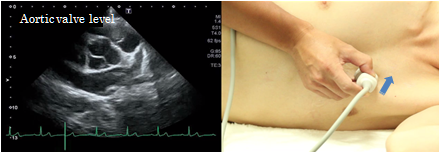

Aortic valve level

At the aortic valve level of the short axis view of the left ventricle, the 3-cusp structure consisting of right coronary cusp of the aortic valve, the left coronary cusp, and the non-coronary cusp can be confirmed. The pulmonary valve can be seen on the right side of the screen and the tricuspid valve is on the left side. This view is used to visualize the cusps of the aortic valve, to measure the aortic valve area. Furthermore, this view visualizes pulmonary valve, tricuspid valve, the origin of the coronary arteries and utilize it for the classification of ventricular septal defects.